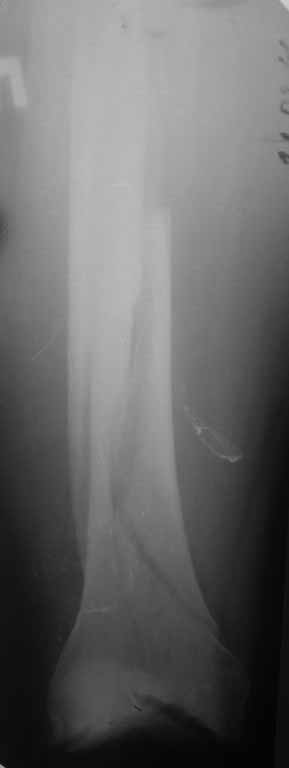

Представляю вам один из наших недавних случаев выполнения малоинвазивного остеосинтеза бедренной кости обычной пластиной 95 градусов.  Длина восстановлена с помощью дистрактора (по сути это основная и б(о)льшая часть репозиции). Произведено два небольших доступа, проведена спица направитель. Рентген-контроль для подтверждения достаточной длины/оси(ЭОП использовался в другой операционной). Создание тунеля обратной стороной фиксатора. Поворот фиксатора, введение клинка по спице. Фиксация проксимального и дистального концов пластины.

Имя     : 1Xpre.JPG

Тип     : image/jpg

Размер  : 32005 байтов

Описание: отсутствует

Url     : http://weborto.net:8080/pipermail/ortho/attachments/20110902/aa3367e1/attachment-0007.jpg